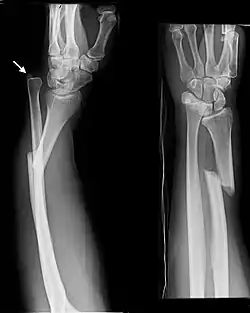

| Monteggia Fracture (type of ulna fracture) | |

- Monteggia fracture - a fracture of the near to elbow end of the ulna with the dislocation of the head of the radius at the elbow joint.[2]

Monteggia Fracture (fracture of proximal ulna) -